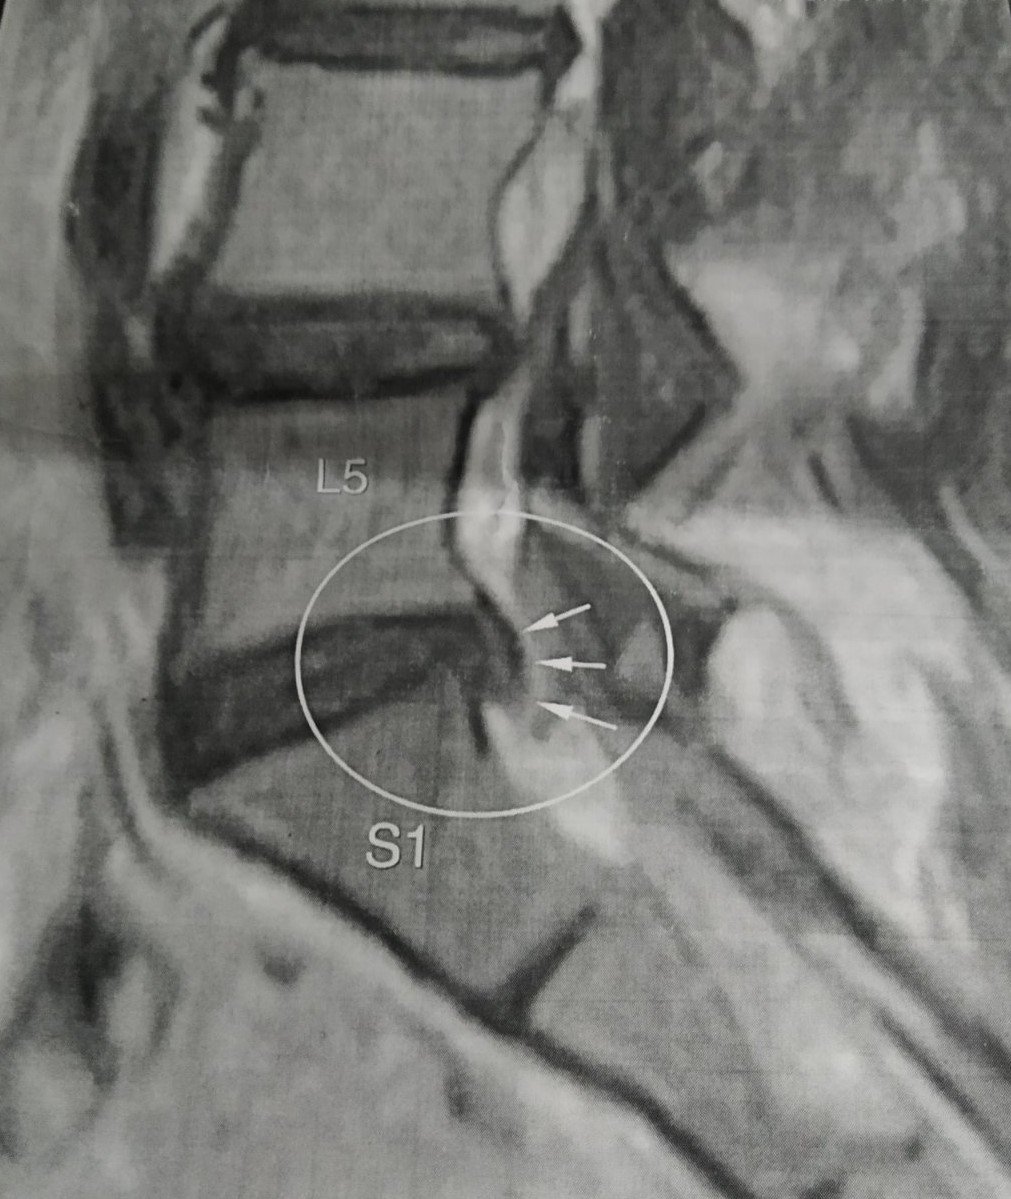

Всередині хребта є порожнина, в якій знаходиться центральна нервова система — спинний мозок. Внаслідок цих хвороб — остеохондроза, спонділоартроза , спондильоза- виникають грижі, протрузії. Це призводить до того, що простір між хребцями звужується. Для повноцінного фукціювання мозку потрібна глюкоза. 90% глюкози із нашого організму потребує головний мозок. Глюкоза в головний мозок поставляється ліквоїдною або цереброспинальною рідиною, яка циркулює в порожнині спинного мозку і яка рухається по хребту під час руху.

Спондилоартроз — патологічні зміни і руйнування міжхребцевих суглобів, які спричиняють порушення їх функції, і як наслідок – виникають сильні больові відчуття. Спондилоартроз мають 80-90% людей похилого віку. Бо більшість людей мало приділяють часу для профілактики захворювань хребта. В першу чергу хвороба вражає міжхребцеві диски (остеохондроз) — зниження їх висоти внаслідок їх перевантаження.

В результаті остеохондрозу формується спондилоартроз і з’являється яскраво виражений больовий синдром і, як захисна реакція організму, виникає спазм (папруження м’язів). Спазмовані м’язи приводять до звуження судин і порушення струму крові в м’язах. При найменшому нездужанні важливо відразу вплинути на м’язовий тонус (розслабити м’язи): масаж, лікувальна фізкультурара, лазня з віником, зігріваючі мазі і вітаміни групи В, сольові ванни, спазмолітики (після консультації лікаря).